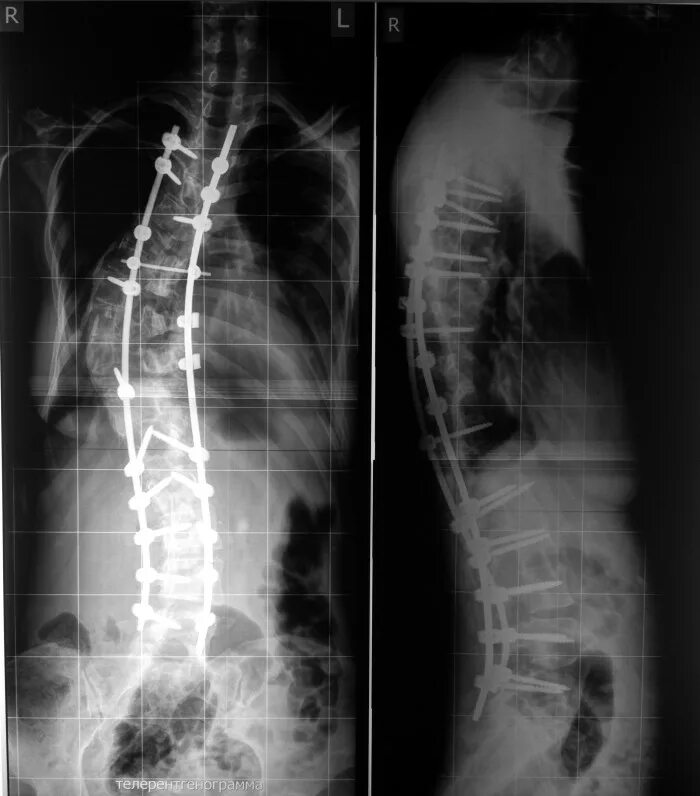

Кифосколиоз мкб